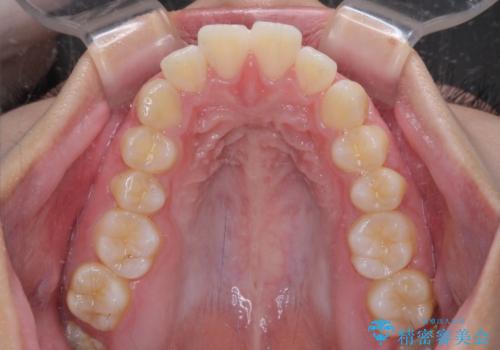

- 上顎前歯が飛び出していて唇がうまく閉じられないとのことで来院された患者様です。

くちばしのように前歯が突出していたため、口元を積極的に引っ込めるために、上下左右の小臼歯4本を抜歯することとしました。

また、上顎歯列が下顎に対して前方位に位置していたため、補助装置を用いて上顎歯列を後方に移動させ、より積極的に口元を下げるようにしました。

上下正中位置を改善するため、左下はイレギュラーに第二小臼歯を抜歯しました。そのため治療期間の長期化が予想されましたが、2年半ほどで期待通りの歯列に仕上げることができました。